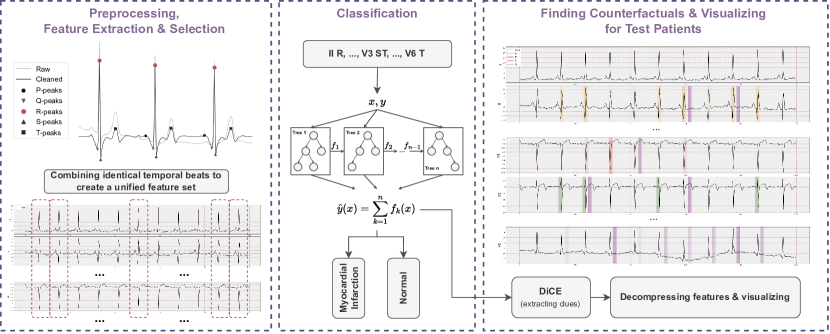

In this section, we present the details of the system we propose. The methods in the system involve several main steps: preprocessing the data, extracting and selecting important ECG signal features, gathering clues, generating reports and producing visualizations (Figure 1).

4.2 Feature Extraction, Feature Selection & Classification

Due to the potential for performance degradation in ML training caused by a high number of features, which could also result in generating insignificant scenarios during counterfactual generation, we aimed to minimize the number of features. To achieve this, we initially employed the recursive feature elimination (RFE) method with the default XGBoost (XGB) algorithm, using the objective parameter ‘binary:logistic’ and the booster parameter ‘gbtree’ with default tree parameters. This process identified 97 features as rank 1. We opted not to perform hyperparameter optimization for the XGB model due to computational constraints, preliminary results indicating that default parameters were sufficient, and our focus on feature engineering instead of model tuning. We believe that this decision was appropriate given the specific context and goals of our research. Following the feature selection, the chosen 97 features underwent further assessment, and their ranking was adjusted based on their importance within the XGB framework (Appendix Figure C.5). We then took a systematic approach to training the model, starting with just 1 feature and gradually adding more, up to the full set of 97 features, documenting the outcomes at each step (Figure 3).

Building on this methodology, counterfactual generations were performed by selecting the top 5, 10, 15, and 20 feature groups. It is important to note that this generation is a post-hoc procedure, independent of the model they are built upon. Furthermore, in the latest feature set, we have employed a hybrid approach, integrating domain expertise with data-driven analysis, to assess the quality of counterfactual visualizations. Following a clinical preliminary analysis, we have incorporated four additional features into the top 20 features with the aim of improving the diagnostic capability of our method for individual cases that might require further localized information.

4.3 VCCE: Visualizing Counterfactual Clues on Electrocardiograms

We have developed a visualization method, VCCE, to enhance the presentation stage of the obtained counterfactual clues to the end-user, i.e., the clinician. This structure involves highlighting counterfactual clues obtained from the patient’s signal in the ECG report. For visualization, we offer various options that allow the display of peaks in chosen regions along with advanced features. These features are computed via amplitude differences and are presented as lines with their distance values overlaid on the ECG signal. Moreover, when visualizing counterfactuals, the more a specific feature is selected in an alternative world, the more it is strongly highlighted on the ECG report.

5.1 Feature Elimination and XGBoost Classification

For the training of the ML model, our initial step involved employing RFE on XGB to reduce the number of features. This process assigned a rank of 1 to 97 features, and we proceeded with our analysis using this subset of selected features. In subsequent stages of our analysis, we computed the importances of these chosen features within the XGB, as depicted in Appendix Figure C.5.

Following an in-depth examination of the selected features, we organized them based on their respective importance scores. Then, we conducted further training on XGB, progressively augmenting the number of features employed in the model (Figure 3). As depicted in Figure 3, we can observe that having a mere 2% score tolerance enables us to reduce the feature count from 86 to 19. This reduction brings benefits when working with counterfactuals.

Through our experimental investigations, we discovered that utilizing 19 features is sufficient for extracting counterfactual instances. A lesser number of features is preferable for counterfactuals as it yields better and more reasonable explanations. To conduct a comprehensive assessment of counterfactuals, we generated distinct scenarios involving sets of 5, 10, 15, and 20 features. This evaluation encompassed considerations such as the time taken for generation (refer to Appendix Figure C.6 and C.7) and a comparative analysis of the most influential features affecting the outcomes. The F1 scores for each feature set are as follows: 81.40% for 5 features, 83.50% for 10 features, 85.83% for 15 features, 86.59% for 20 features, and 88.47% for 97 features.